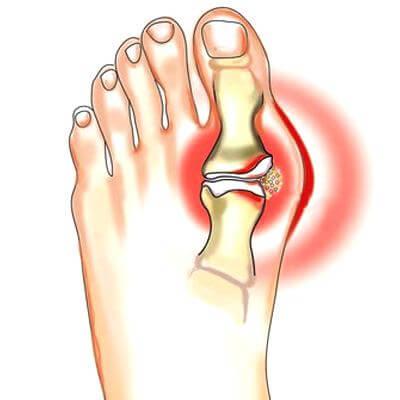

Данный этап подагры называют хроническим. У человека в организме уже образуются кристаллы из мочевой кислоты. Они похожи на небольшие выступы на коже. Впоследствии выступ может увеличиваться до крупных размеров и полностью деформировать близлежащий сустав. Третья стадия подагры также приводит к мочекаменной болезни. Вот симптомы данного этапа болезни:

- Сустав начинает краснеть и воспаляться;

- Появляется сильная боль;

- В теле образуются тофусы;

- Подвижность сустава снижается;

- У пациента повышается температура тела.

Необходимо помнить, что любая боль появляется из-за отложения кристаллов в суставе. Они начинают травмировать ткань и задевать хрящи. Это негативно воздействует на нервные окончания и приводит к боли. Чтобы избавиться от такого симптома, нужно сразу же начинать лечение подагры комплексными методами.

На третьей стадии кожа в области пораженного сустава становится красной. В момент обострения отек виден внешне. В момент ремиссии такой симптом проходит.

К пораженному участку приливает большое количество крови, что и приводит к покраснению. Из-за воздействия мочевой кислоты повышается проницаемость в сосудистых стенках. Это провоцирует отек кожи.

Появление тофусов в организме

Именно в момент подагры появляются тофусы. Это соли мочевой кислоты, которые располагаются под кожей. Они медленно разрастаются и могут даже не проявлятся в первые 3 года заболевания. Если в поврежденной зоне нарушено кровообращение, тогда над тофусами образуются опасные язвы. Необходимо выделить места, в которых чаще всего могут возникнуть отложения солей: